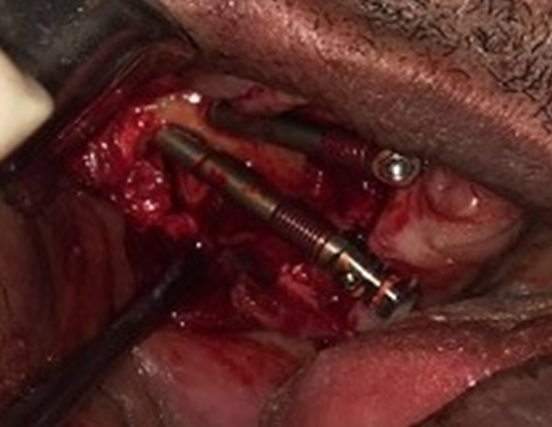

Então, seguiu-se a instalação de dois implantes zigomáticos DSP Biomedical 40 mm e 45 mm (Campo Largo, PR) do lado direito da maxila. Para instalação dos implantes zigomáticos utilizou-se a Técnica Exteriorizada de Migliorança11, possibilitando que a sequência de fresagem seja totalmente visível. Nessa técnica, as sinusopatias não ocorrem, pois as fixações zigomáticas são instaladas externamente ao seio maxilar, e a ausência de antrotomia impede que haja infecção do seio maxilar e que haja invaginação de tecidos moles para o interior deste (Figuras 5 e 6). Ao penetrar a broca pela vertente palatina do rebordo devido a severa atrofia do remanescente ósseo na maxila, a mesma se rompeu, caracterizando a Técnica de Migliorança modificada12.

Todos os implantes obtiveram boa estabilidade inicial (acima de 45 N/cm), o que permitiu a submissão dos mesmos à carga imediata, por isso é realizada a instalação dos intermediários protéticos com torque de 20N/cm no ato cirúrgico. Com os pilares protéticos instalados, foi realizada a sutura com fio reabsorvível, sempre atentando para a completa coaptação dos bordos do retalho a fim de evitar a entrada de material de moldagem durante os procedimentos protéticos (Figura 7).